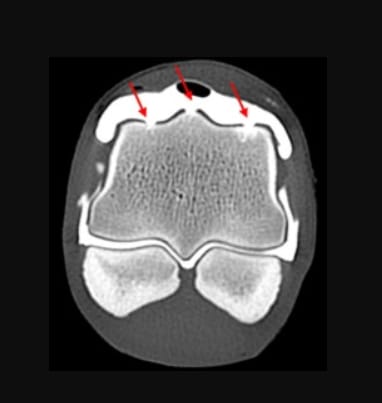

CTA scan, at the volume of iodinated contrast of 20 ml, displayed in a transverse plane generated via multiplanar reconstruction. Note the site of the defects in the metacarpal medial and lateral condyles, and sagittal ridge were indicated by the red arrows. Images were created using the MPR function in a bone window (WL: 553 WW: 2613) from bone kernel reconstruction.